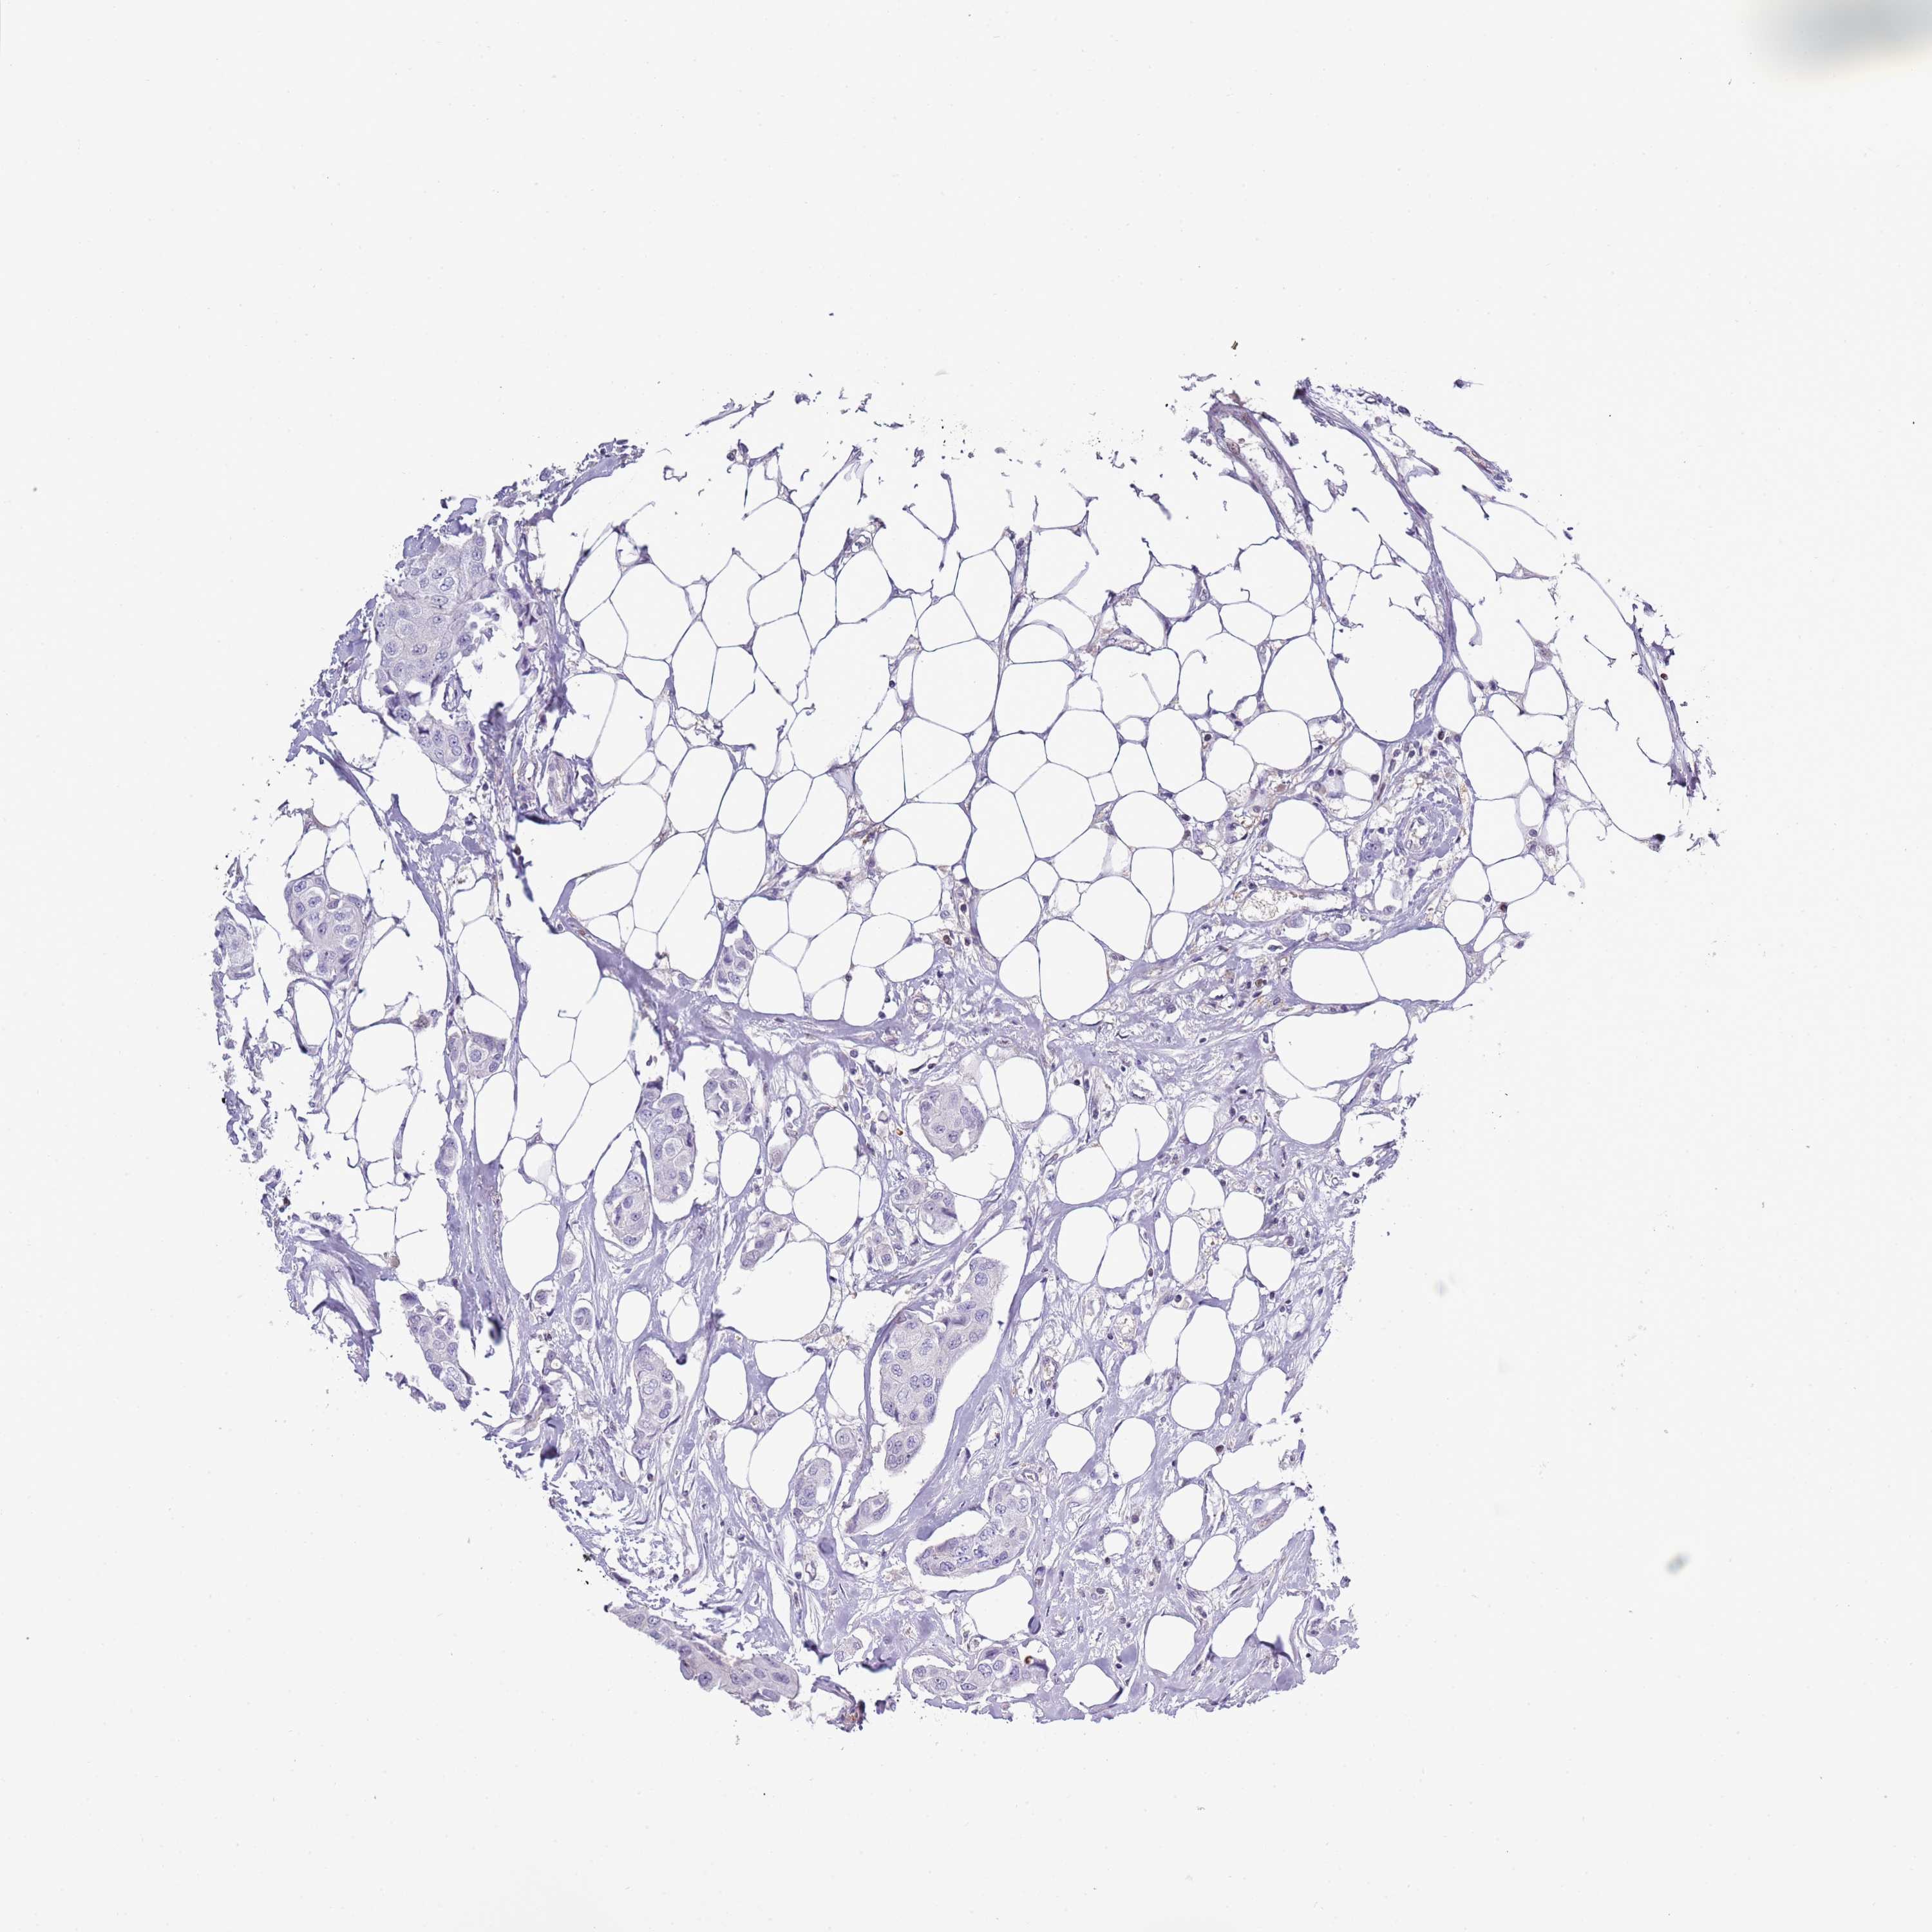

CANCER BREAST CANCER Show tissue menu

Breast cancer

Human cancer